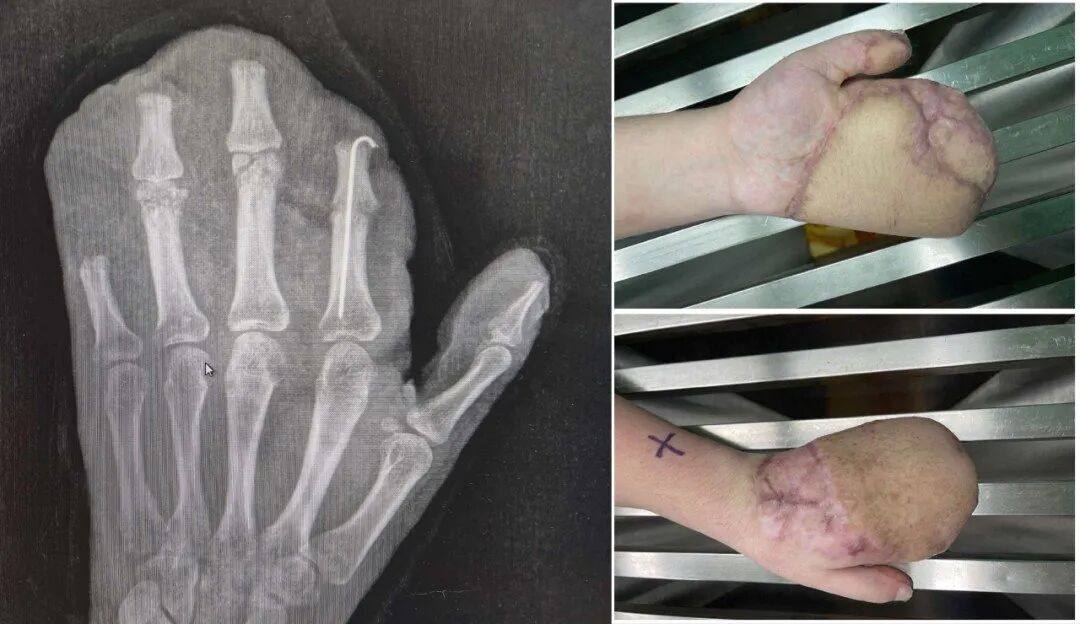

医生诊断他为:1.左手掌、手背,示指中指环指小指掌侧及背侧皮肤毁损脱套伤;2.左手掌、手背及各指肌腱神经血管损伤;3.左手多发性开放性指骨骨折伴毁损;4.左拇指末节指腹皮肤、软组织缺损;5.左拇指固有神经断裂;6.左拇指甲床裂伤。

医院随即为小王做了手术,术中,医生们完成了彻底的清创,修复了骨折、断裂的肌腱与神经。

为覆盖巨大创面,医生启用了经典的“腹部带蒂皮瓣”,将断手“寄养”在了带有自身血供的腹部皮肤上,为后续所有修复提供了生存的土壤。

经过近一个月的“腹手相连”,皮瓣在手部建立了新的血运。医生们进行了“断蒂”手术,让手从腹部独立,患者也获得了活动自由,为功能锻炼打下基础。等待皮瓣完全稳定后,医生们开始了功能重塑。手术将臃肿的皮瓣进行修薄塑形,并进行了首次分指术,把粘连在一起的手指分开,同时取出了已愈合的骨折内固定物。